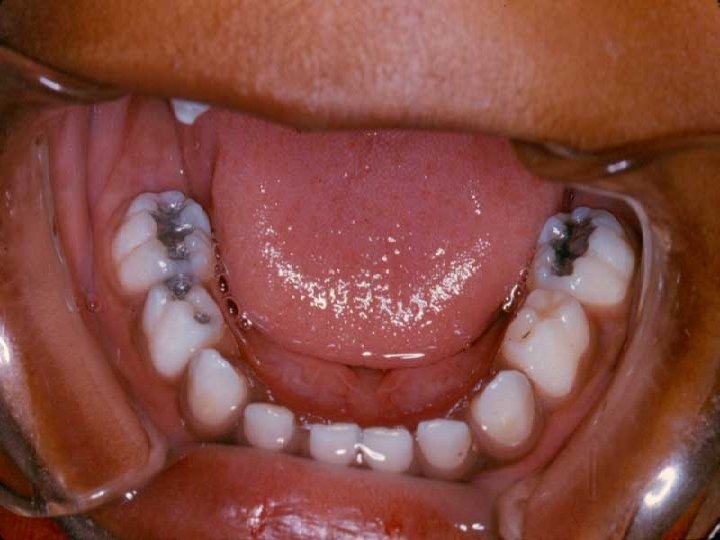

Preventive Materials 1. Fluoride gels, foam and varnish: • Used for remineralisation of decalcified enamel and incipient caries. 2. Sealants: • Indicated for preventing and arresting incipient lesions. • Available as clear or white, filled or unfilled, containing Fluoride or not.